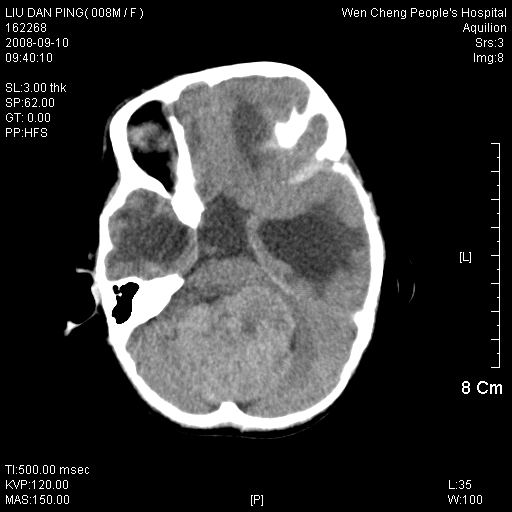

以下是引用卜一在2008-9-10 16:21:00的发言:[br]髓母细胞瘤伴梗阻性脑积水!支持![br]髓母细胞瘤特点:—般直径大于3.5cm,位于后颅凹中线之小脑蚓部。累及上蚓部的肿瘤延伸到小脑幕切迹之上,ct平扫肿瘤多呈均匀一致的高或等密度病灶,增强检查呈均匀一致的强化。病灶中有小坏死时,平扫亦可呈不均匀之混杂密度,注药后有增强。[br]

以下是引用zjzjr在2008-9-10 15:09:00的发言:[br]髓母细胞瘤伴梗阻性脑积水.